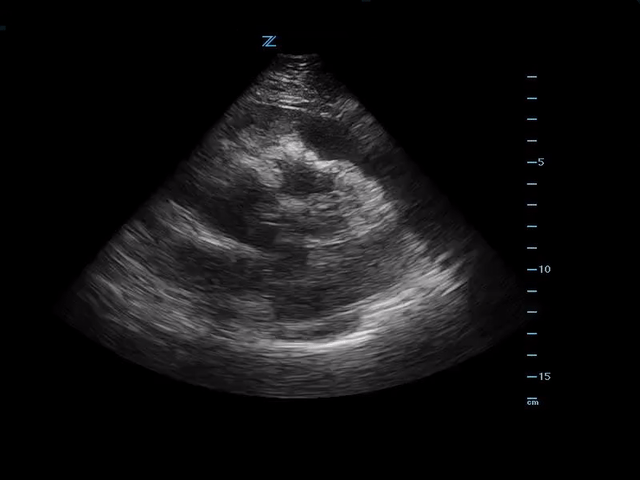

Bedside ultrasound showed the following:

Large pericardial effusion in PLAX view.